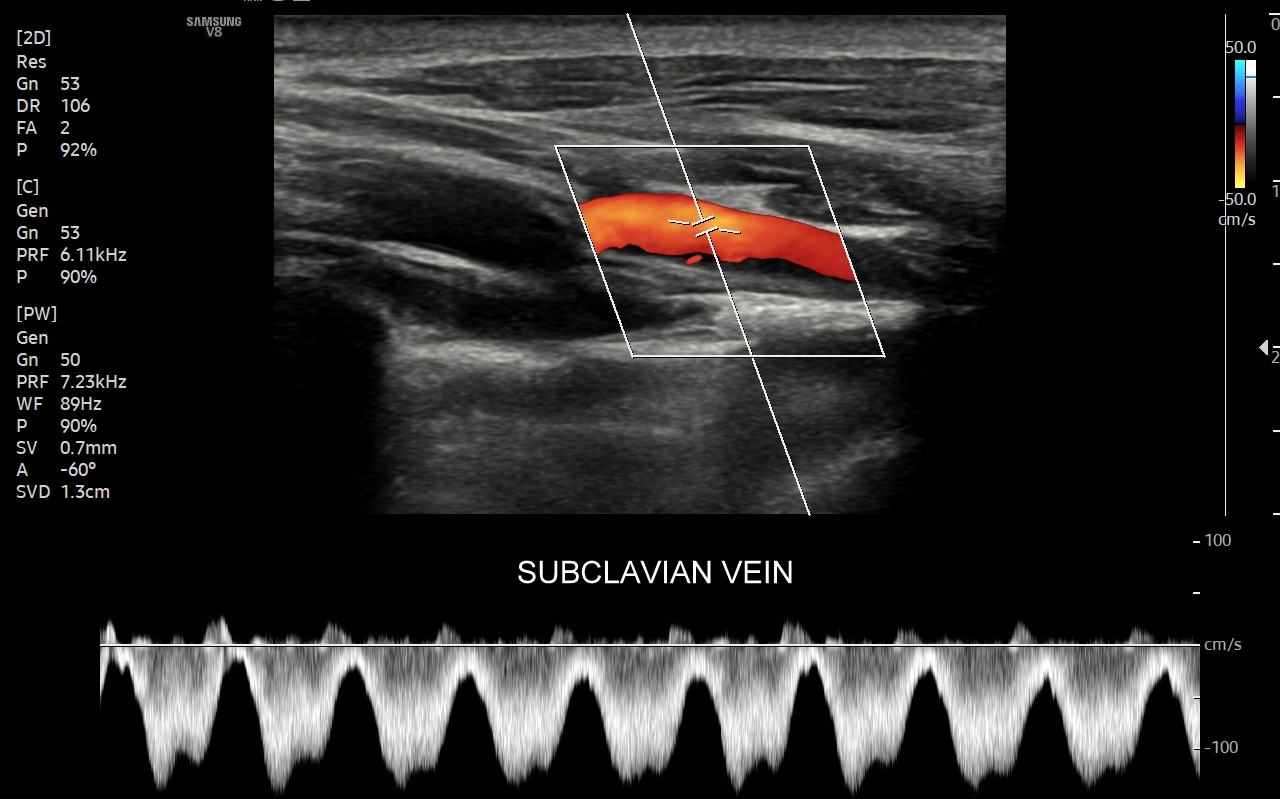

Czym jest zakrzepica żył? Zakrzepica żylna polega na powstaniu skrzepu wewnątrz naczynia żylnego i wtórnym rozwoju stanu zapalnego w okolicy naczynia. Choroba dotyczyć może układu powierzchownego żył lub żylaków, a w tym wypadku nie jest zwykle stanem niebezpiecznym; a także układu głębokiego żył, co z kolei jest stanem potencjalnie zagrażającym życiu, gdyż może sprowokować zatorowość płucną. Zakrzepica żył głębokich (ang. deep venous thrombosis DVT) częściej występuje w obrębie żył kończyn dolnych, następnie w obrębie żył biodrowych, rzadziej w żyle podobojczykowej i żyłach głębokich kończyny górnej. Przyczyny zakrzepicy żylnej są różnorodne i obejmują m. in. długie podróże, długotrwałe unieruchomienie, operacje ortopedyczne, chirurgiczne i szczękowe, urazy tkanek miękkich oraz złamania kości, genetycznie uwarunkowane trombofilie, nowotwory złośliwe, odwodnienie, infekcje miejscowe i ogólnoustrojowe. W przypadku zakrzepicy żyły podobojczykowej klasyczną jej przyczyną jest ucisk; w swojej praktyce klinicznej dr Szczepański spotkał się z zakrzepicą podobojczykową wywołaną m. in. przez ciężki plecak, wyciskanie sztangi na siłowni, czy przez uprawianie wspinaczki skałkowej. W warunkach szpitalnych zakrzepica żyły podobojczykowej lub żyły szyjnej wewnętrznej może pojawić się w wyniku zakładania cewników dożylnych. Sprawne wykrycie zakrzepicy w badaniu USG, a następnie wdrożenie odpowiedniej terapii uchronić może pacjenta przed powikłaniami ostrymi (np. zator płucny), jak i opóźnionymi (np. zespół pozakrzepowy).

USG Doppler żył szyjnych i kończyn górnych

Badanie USG Doppler żył szyjnych, podobojczykowych i żył kończyn górnych najczęściej wykonywane jest z powodu spontanicznych zakrzepów pojawiających się w przebiegu takich schorzeń jak odwodnienie, nadużycie napojów „energetycznych”, zespoły uciskowe, zespół górnego otworu klatki piersiowej, choroby nowotworowe i mieloproliferacyjne, trombofilia, czy jatrogenne powikłania cewnikowania żył. U osób zdrowych, tj. bez obciążeń trombofilnych, zakrzepica w zakresie żył obręczy kończyny górnej zwykle występuje jako powikłanie ucisku, np. przez mięśnie u osób podnoszących ciężary na siłowni albo przez ramiączka ciężkiego plecaka podczas wędrówek krajoznawczych. Objawami zakrzepicy żyły ramiennej, pachowej, podobojczykowej, czy żylnego pnia ramienno-głowowego zwykle są uczucie dyskomfortu w kończynie górnej, ból, ograniczenie ruchomości, zasinienie i obrzęk kończyny górnej, pojawienie się poszerzonych naczynek na ścianie klatki piersiowej.

Podczas najczęściej przeprowadzanego badania, tj. USG Doppler kończyn dolnych, oceniane są żyły głębokie oraz powierzchowne na całej długości kończyny – od stóp aż do pachwiny. Czasami mogą zaistnieć wskazania do rozszerzenia badania na wyższy poziom układu żylnego, tj. na żyły biodrowe w miednicy i żyłę główną dolną w jamie brzusznej. Badanie USG żył jest badaniem dynamicznym, tzn. oprócz oceny wyglądu żył wykonuje się różnorodne próby czynnościowe, takie jak kompresja, głębokie oddychanie, próba Valsavy, podczas których rejestruje się przepływy krwi w żyłach.

W przypadku oceny wydolności żył oraz kwalifikacji Pacjenta do zabiegu na żyłach lub na żylakach kończyn dolnych dynamiczne badanie dopplerowskie żył wykonuje się także w pozycji pionowej. Przy opisanych próbach czynnościowych wykorzystuje się specjalne właściwości sprzętu USG, tj. tryby badań dopplerowskich, tryby duplex i triplex, a także angografię sonograficzną dostępną w aparatach wysokiej klasy.